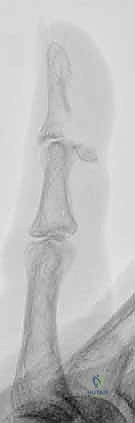

FIG 1 • Lateral radiographs usually are the most helpful in identifying a mallet fracture. Note that in this image, the avulsed fragment includes more than 50% of the articular surface. There is no significant volar subluxation in this case.

- Mallet Fracture: Lateral radiographs are most helpful for identifying the bony avulsion fragment, its size, and any associated joint subluxation. We need to estimate the percentage of articular surface involved.